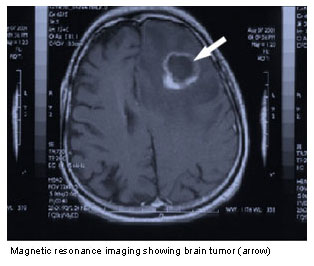

I just read my nephew’s post on CaringBridge about his dad who has been battling a brain tumor for the past year. This man is a man of faith; God is very present in his life and in the life of his family. The prognosis for this kind of inoperable tumor isn’t great, but to those who dwell in the shadow of the Most High God, nothing is impossible!

There is no lying down and letting this foe take D. down, Praise God! D. has been living out this verse — he’s been resisting, standing his ground against this evil with every ounce of his strength. After he’s done everything the doctors have told him to do, he soaks in the word of God and is standing immovable in his faith, even in the face of the Goliath-sized tumor in his head.